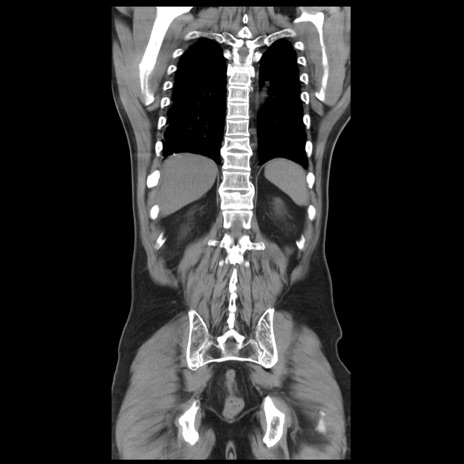

症例20(冠状断像)

【症例】 60歳代男性

【主訴】 腹部膨満、嘔吐

【現病歴】5日前頃より倦怠感を認め食事量減少し4日前の朝嘔吐、食事摂取困難となった。 3日前近医受診し点滴施行され整腸剤などを処方された。 当日他院を受診し、腹部膨満著明、炎症反応の上昇(CRP10.8、WBC11200)あり、紹介受診となる。

【身体所見】 意識JCS1 受け答えがはっきりしないBP 111/57mHg、 P 67bpm、、BT35.2°C、SpO2 97%(RA)、 腹部:膨隆、打診で鼓音あり、全体的に圧痛有り、腸蠕動音(-)、反跳痛ははっきりせず。

【データ】WBC 11400、CRP 14.20